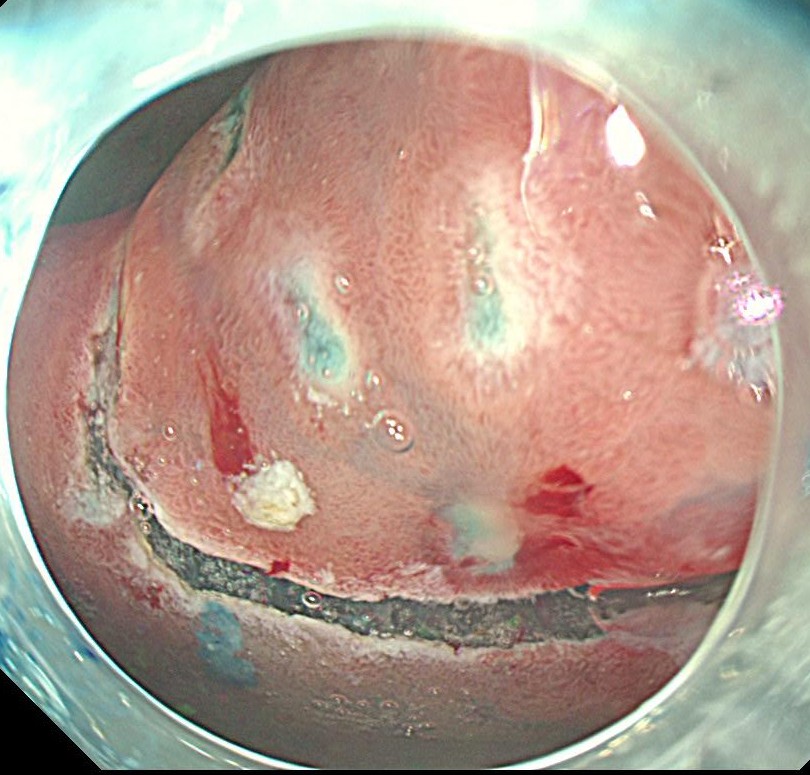

切除後の粘膜欠損部です。

摘出標本です。高分化型粘膜内癌であり、根治切除と診断されました。